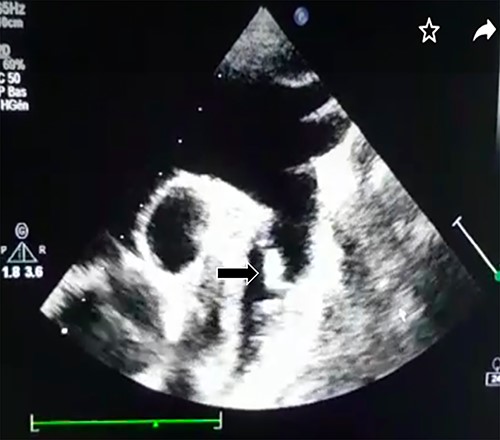

Transthoracic echocardiography revealed a large PDA (10 mm) with left-to-right shunt and a fixed structure on the wall of the pulmonary artery, with erratic movement indicative of a vegetation (Fig. 1), and mobile vegetation attached to the wall of the descending aorta in the supra-sternal view (Fig. 2) and a left ventricle with conserved systolic function and 55-mm end-diastolic diameter.

Large PDA and a fixed structure on the wall of the pulmonary artery.